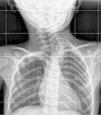

A patient aged 4 years presented with suspected torticollis with onset several years prior that was refractory to treatment. The examination revealed a left cervical hump associated with limitations in turning and tilting that was assessed with a cervical X-ray (Fig. 1).